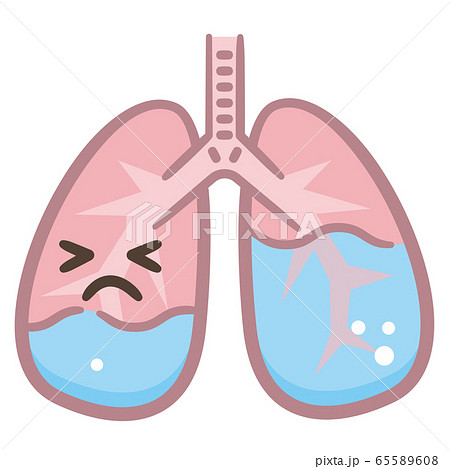

水が溜まった肺のイラスト素材

不健康 肺 水が貯まる イラスト イラスト素材 フォトライブラリー Photolibrary

肺水腫のイラスト素材

肺水腫のイラスト素材